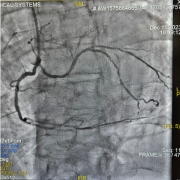

Quiz Hémodynamique

Réalisé par Cécile Balere et Laetitia Pedrico, Clinique Pasteur, Toulouse -

Ce quiz est proposé par Fanny Villanova, GHEF, Jossigny -